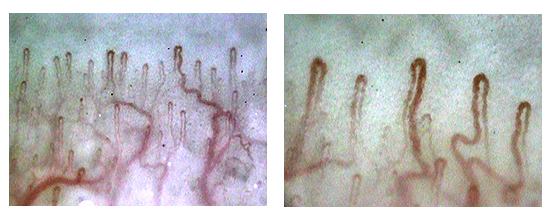

毛細血管スコープ Bscan-ZD 研究セット|顕微鏡・光学機器|製品 大画面の9インチモニター付きの「新品未使用品」の血流スコープです。(98,553円の商品をヤフオク専用の特別価格で販売しています。)他の商品は倍率が低いため、血流が見えにくいという欠点がありました。そのため、このモデルに買い換えた方も中にはいらっしゃっいました。この商品は市販品の中では「最も高倍率」の血流スコープになります。スマホのカメラに例えると「望遠レンズ」になりますので、大きく見ることができます。また、血流スコープの見やすさはレンズの大きさに比例します。以前、購入された方から「20万円する商品よりもよく見える!」との感想を頂きましたが、その理由は、鏡筒(レンズ)が大きいからです。安いスマホのカメラは画質が悪く、iPhoneのカメラの画質がいい理由の1つは、レンズが大きいからです。他社の商品よりも、くっきりと大きく写りますので、血流の流れを鮮明に確認する事ができます。1枚目から4枚目の商品の写真は、仕様変更前の写真になります。商品の改良で、下部のレンズが少し大きくなり、更に見やすくなりました。お送りする商品の写真は5枚目~9枚目をご確認ください。付属のモニターでも「ipad mini」より大きな画面で見ることができます。また、テレビのRCA端子に接続して、大画面テレビで見ることも可能です。(コードを購入する必要はありません。)日本語の説明書が付いていますので、接続に不安がある方もご安心下さい。ピントを合わせると、かなり鮮明に写りますので、運動後に確認をすると、血流がかなり早くなっていることもしっかりと確認できます。また、高倍率のため、ゴースト血管のチェックもできます。実際の使い方ですが、薬指の爪の甘皮の部分にオイルを付けて、毛細血管を観察します。オイルはどのオイルでも問題なく見ることができますので、家庭にあるオリーブオイルや食用油をご利用下さい。持ち運びをする時は、付属のアルミニウムケースをご使用下さい。なお、テレビで見るときは白黒になりますが、カラーで見たい方は変換器を購入すると、カラーで見ることができます。円安でかなり仕入れ価格が上がっていますが、価格をかなり抑えて販売していますので、よろしくお願い致します。